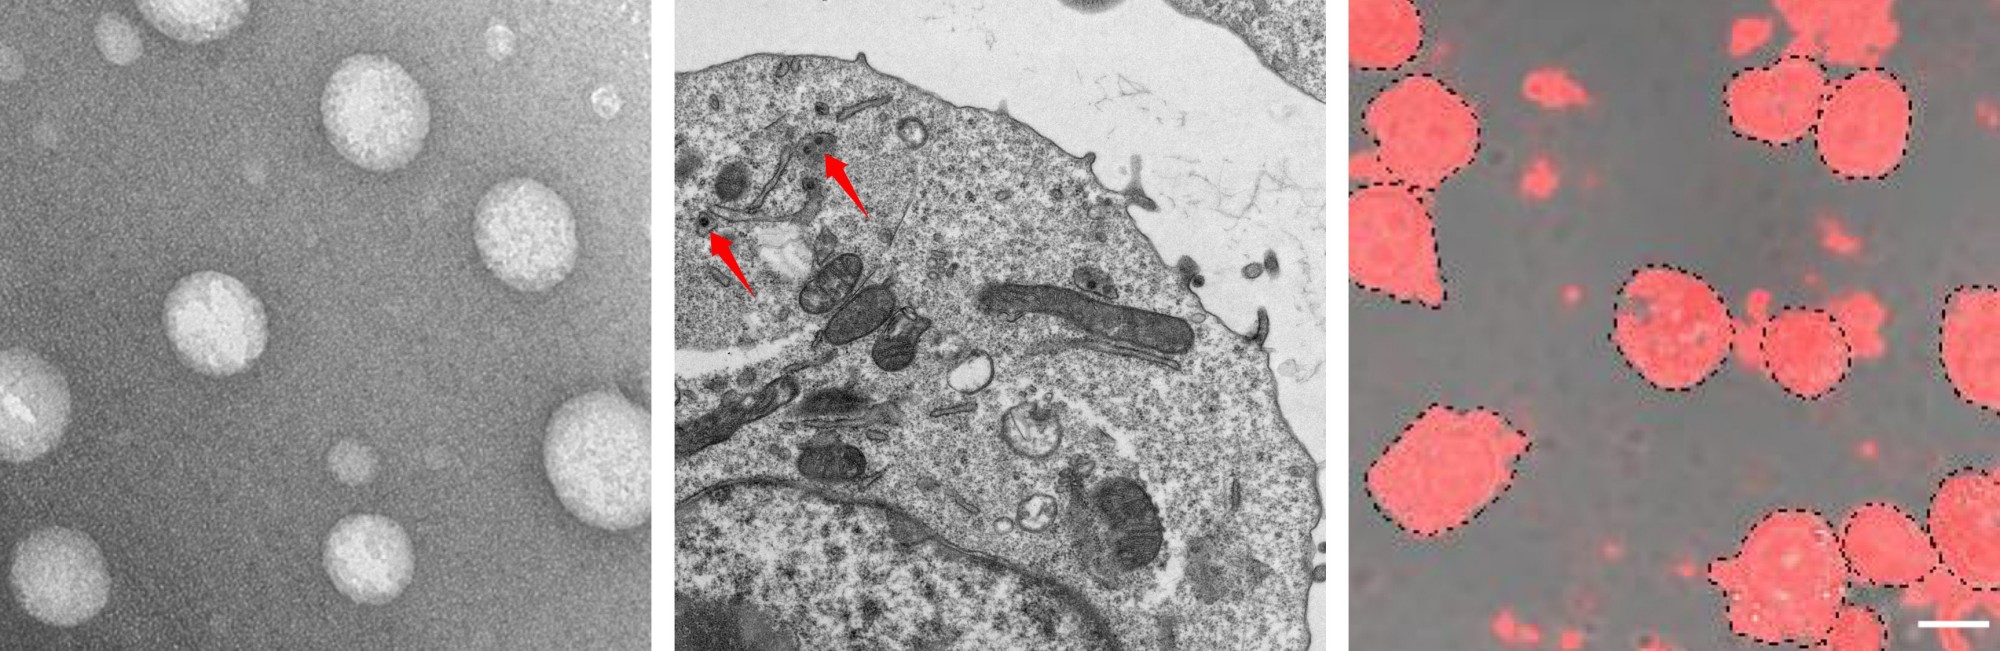

构建基因纳米载体系统进行原位基因编辑和定向改造免疫细胞,用于肿瘤或自身免疫性疾病治疗。

纳米材料细胞搭便车